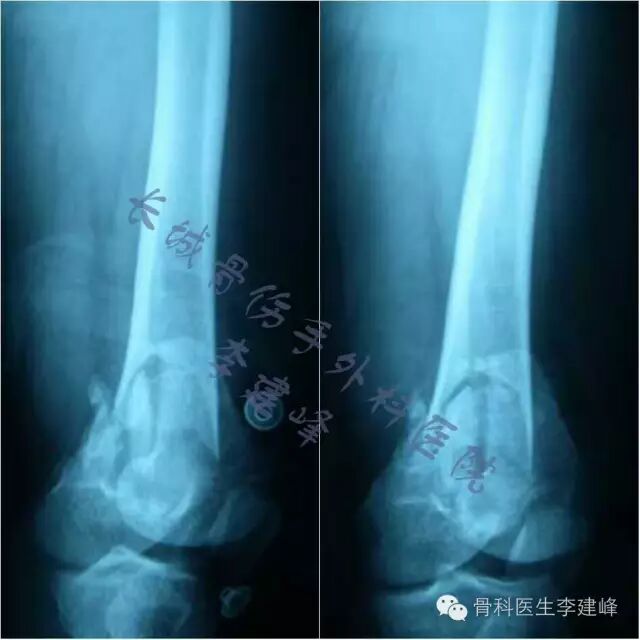

Six case :

术前

术后